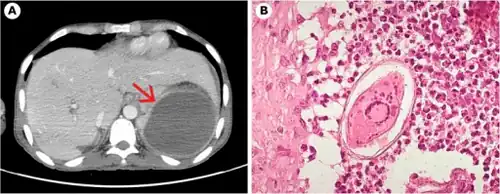

Schistosome eggs, which may become lodged within the hosts tissues, are the major cause of pathology in schistosomiasis. Some of the deposited eggs reach the outside environment by passing through the wall of the intestine; the rest are swept into the circulation and are filtered out in the periportal tracts of the liver, resulting in periportal fibrosis. Onset of egg laying in humans is sometimes associated with an onset of fever (Katayama fever). This "acute schistosomiasis" is not, however, as important as the chronic forms of the disease. For S. mansoni and S. japonicum, these are "intestinal" and "hepatic schistosomiasis", associated with formation of granulomas around trapped eggs lodged in the intestinal wall or in the liver, respectively. The hepatic form of the disease is the most important, granulomas here giving rise to fibrosis of the liver and hepatosplenomegaly in severe cases. Symptoms and signs depend on the number and location of eggs trapped in the tissues. Initially, the inflammatory reaction is readily reversible. In the latter stages of the disease, the pathology is associated with collagen deposition and fibrosis, resulting in organ damage that may be only partially reversible.[52]

Granuloma formation is initiated by antigens secreted by the miracidium through microscopic pores within the rigid egg shell, and the immune response to granuloma, rather than the direct action of egg antigens, causes the symptoms.[53] The granulomas formed around the eggs impair blood flow in the liver and, as a consequence, induce portal hypertension. With time, collateral circulation is formed and the eggs disseminate into the lungs, where they cause more granulomas, pulmonary arteritis and, later, cor pulmonale. A contributory factor to portal hypertension is Symmers' fibrosis, which develops around branches of the portal veins. This fibrosis occurs only many years after the infection and is presumed to be caused in part by soluble egg antigens and various immune cells that react to them.[54]